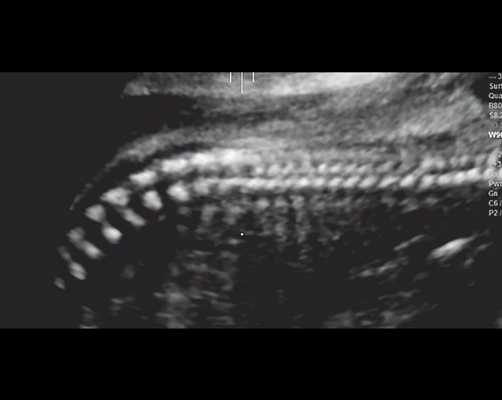

г) Уплощенные тела позвонков; показано увеличенное расстояние между позвонками.

| Набл. 4. 26,5 нед? | БПР - 22,6 нед. ОГ - 22,6 нед. Форма - трилистник (рис. 4а). Боковые желудочки - 22 мм, высокий лоб, расширенный родничок, сагиттальный шов (рис. 4б). | Торакоабдоминальное соотношение - 65,7% (рис. 4в). Окружность груди - среднее для 23 нед. Колоколообразная форма. | ДБ - 23 мм (51% от должной). Остальные кости - 50% для 15-17 нед. Нормальная установка пальцев кисти (рис. 4б). | Уплощенные тела поясничных позвонков (рис. 4г). |

Так, в наблюдении 4 наряду с узкой грудной клеткой и микромелией наличие типичной формы головы в виде трилистника у плода позволило без трудностей установить диагноз ТД II типа.

В остальных трех наблюдениях деформация укороченных бедренных костей на фоне характерных признаков остеохондроплазий позволила предположить ТД I типа. В то же время эти наблюдения требовали проведения дифференциальной диагностики с рядом скелетных дисплазий.